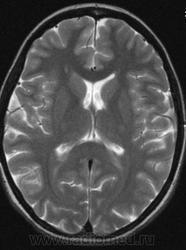

Можно ли  трактовать участок повышенного МР-сигнала по Т2 в правой лобной доле как участок перивентрикулярного глиоза?

Привожу сканы женщины 28 лет без особых жалоб (первые три скана).

Большое спасибо. Да, симметричная линейная паравентрикулярная структура в области передних рогов встречается часто, на что обычно не обращаю внимания. В этом случае смутила ее асимметричность (особенно на Coг. срезах), если думать что это Вирхова-Робина, то возможно это слабо выраженный периваскулярный глиоз.

Иногда у пациентов с дисциркулятонной энцефалопатией по периферии расширенных периваскулярных пространств встречала линейное повышение нтенсивности МР-сигнала на Tirm, расценивала как периваскулярый глиоз, и у нескольких пациентов перенесших перинатальную энцефалопатию видела относительно симметричные зоны паравентрикулярного глиоза резидуального характера в области задних и иногда передних рогов. Поэтому и задумалась, увидив такую асимметричность интенсивности сигнала в этом случае, заподозрив "нерезко выраженный" глиоз справа.